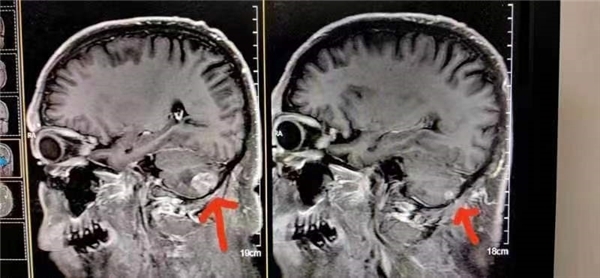

案例24、肺小细胞肺癌脑转移

患者在北京301医院检查治疗结果左脑肿瘤大于右脑肿瘤,陈海林采取采取纯中药的临床治疗,经三个月的治疗,于2023年6月28日的颅脑磁共振平扫十增强:1:右侧小脑转移瘤复查与2o23年3月9日MR片对比,病变基本消失。这个结果连301医院的都声称是奇迹。